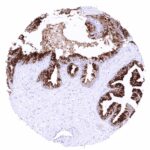

| Lymph node | Membranous CD70 staining of variable intensity in subsets of inflammatory cells (mostly lymphocytes). Most CD70 positive cells are interfollicular. | |

| Tonsil | Membranous CD70 staining of variable intensity in subsets of inflammatory cells (mostly lymphocytes). Most CD70 positive cells are interfollicular. Squamous epithelium remains CD70 negative. | |

CD70 expression is most commonly seen in different types of lymphoma and in clear cell renal cell carcinoma. Other cancer types have also been described to express CD70 at lower frequency.